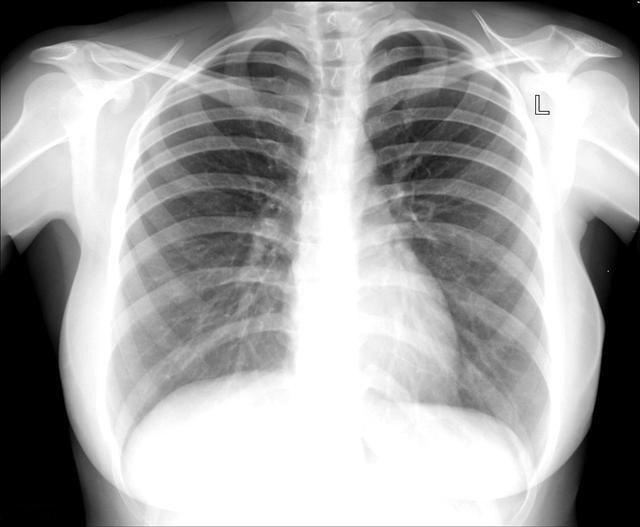

对于检查项目选择的问题,我之前也有介绍,很多人怕辐射大,比较愿意选择胸片检查,但事实上胸片并非没有辐射,但拍摄出来的片子对于早期肺部肿瘤的发现折扣比较大,主要因为胸片分辨率低,对于1cm以下的早期肺癌容易漏诊,另外胸部的结构相互重叠,病灶极容易被挡在某些结构之后而发现不了,而且做了胸片如果发现问题,仍然需要胸部CT进一步观察其大小密度与周围组织的关系以及具体的位置等情况。